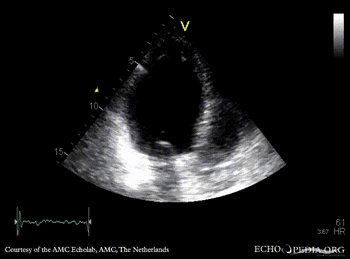

Infarction of posterior and inferior wall

Courtesy of: AMC Echolab, AMC, The Netherlands

E00524.gif E00525.gif

PLAX: dilated left ventricle, akinesia of posterior wall PSAX: akinesia of posterior and inferior wall